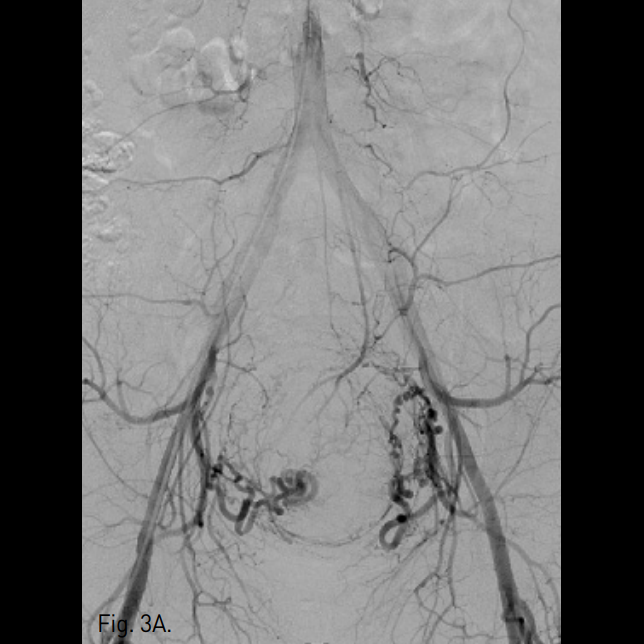

질초음파 검사에서 자궁전벽에 5.5cm × 5.1cm의 자궁근종이 발견됨(Fig. 1). MRI상 자궁전벽에서 기저부까지 근육층에 국한되어 있으며 최대 직경 약 6cm인 자궁근종이 보였다(Fig. 2) 자궁동맥조영술상 비대해진 양측 자궁동맥이 관찰되었고(Fig. 3A, B), 양측 자궁동맥을 polyv inyl alcohol particle과 gelfoam을 이용하여 색전한 후 시행한 자궁동맥조영술에서 자궁동맥이 보이지 않았다(Fig. 3C, D).

Fig. 3

A. Pelvic angiography shows bilateral hypertrophied uterine arteries.

B. Pelvic angiography shows a hypervascular tumor staining of the uterine fibroid.

C, D. After uterine ar tery embolization, hypertrophied uterine artery could not be seen.